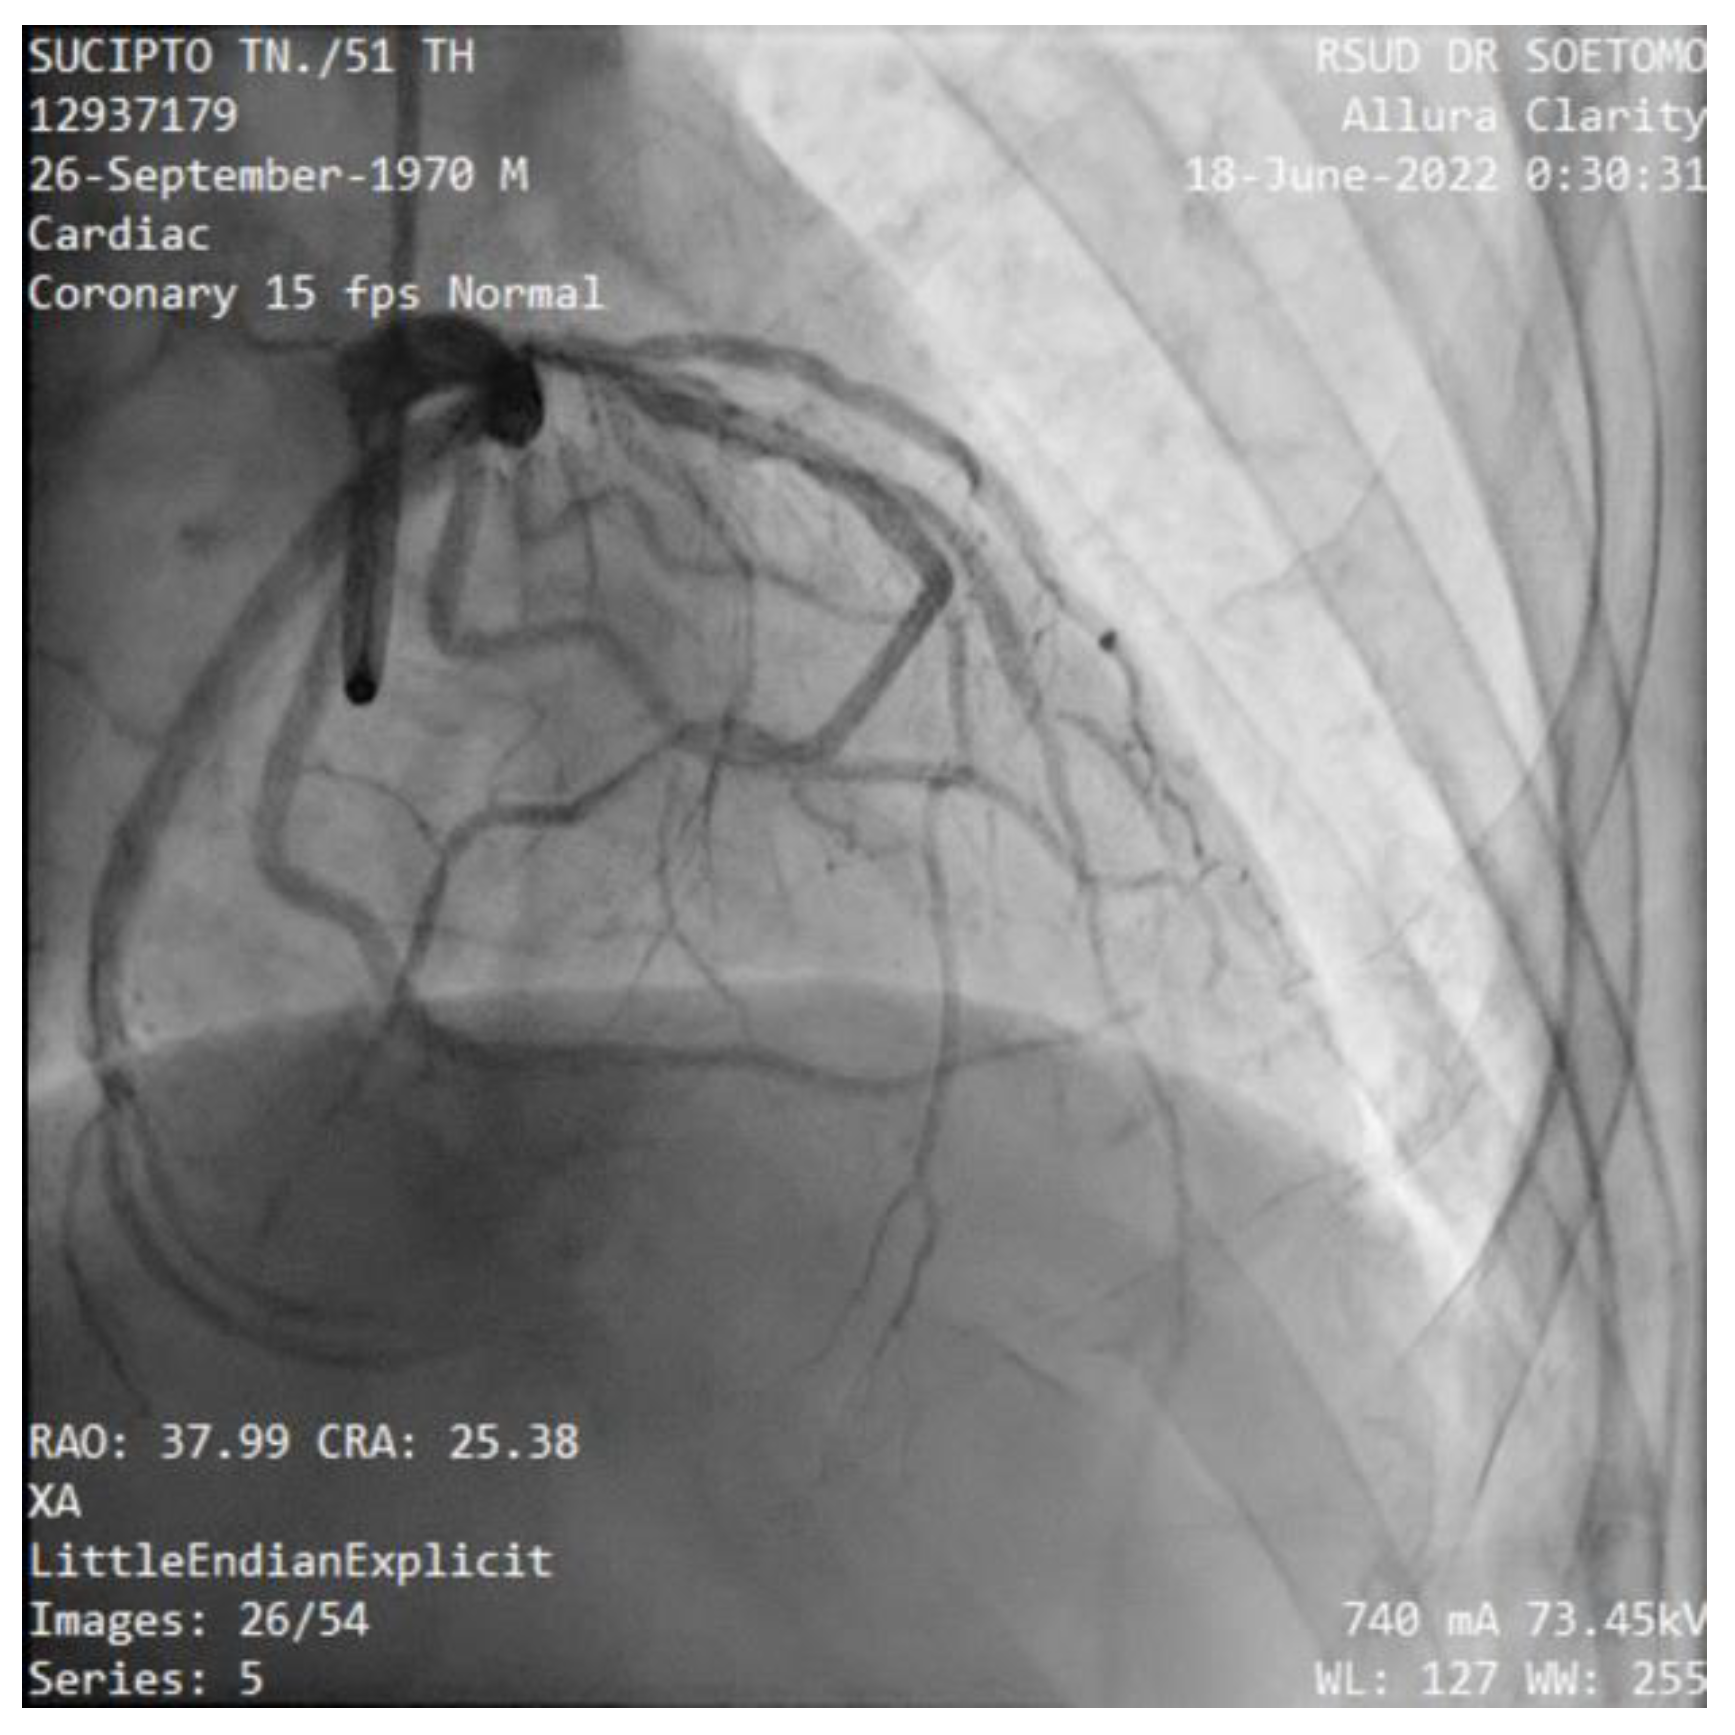

The patient was scheduled for primary percutaneous coronary intervention. Coronary angiography was performed angiography of the left coronary artery revealed a normal LMCA which divided into LAD and LCx (Figure 6). The proximal LAD was giving branch to the RCA, whilst the mid portion of LAD was critically stenosis. The thrombus was aspirated stented in mid LAD with subsequent TIMI 3 flow distally (Figure 8). The patient had an uneventful course after the intervention and was discharged in stable condition after 3 days.

Figure 6. Case #2: The angiography shows a normal LMCA which divided into LAD and LCx. There are a 99% stenosis of mid-LAD and the RCA originates from proximal-LAD.

Preprints 94484 g006

Figure 7. Case #2: The RCA originates from the proximal-LAD.